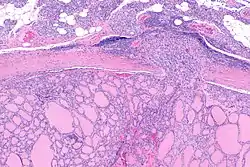

![]() سرطان الغدة الدرقية الجريبي | |